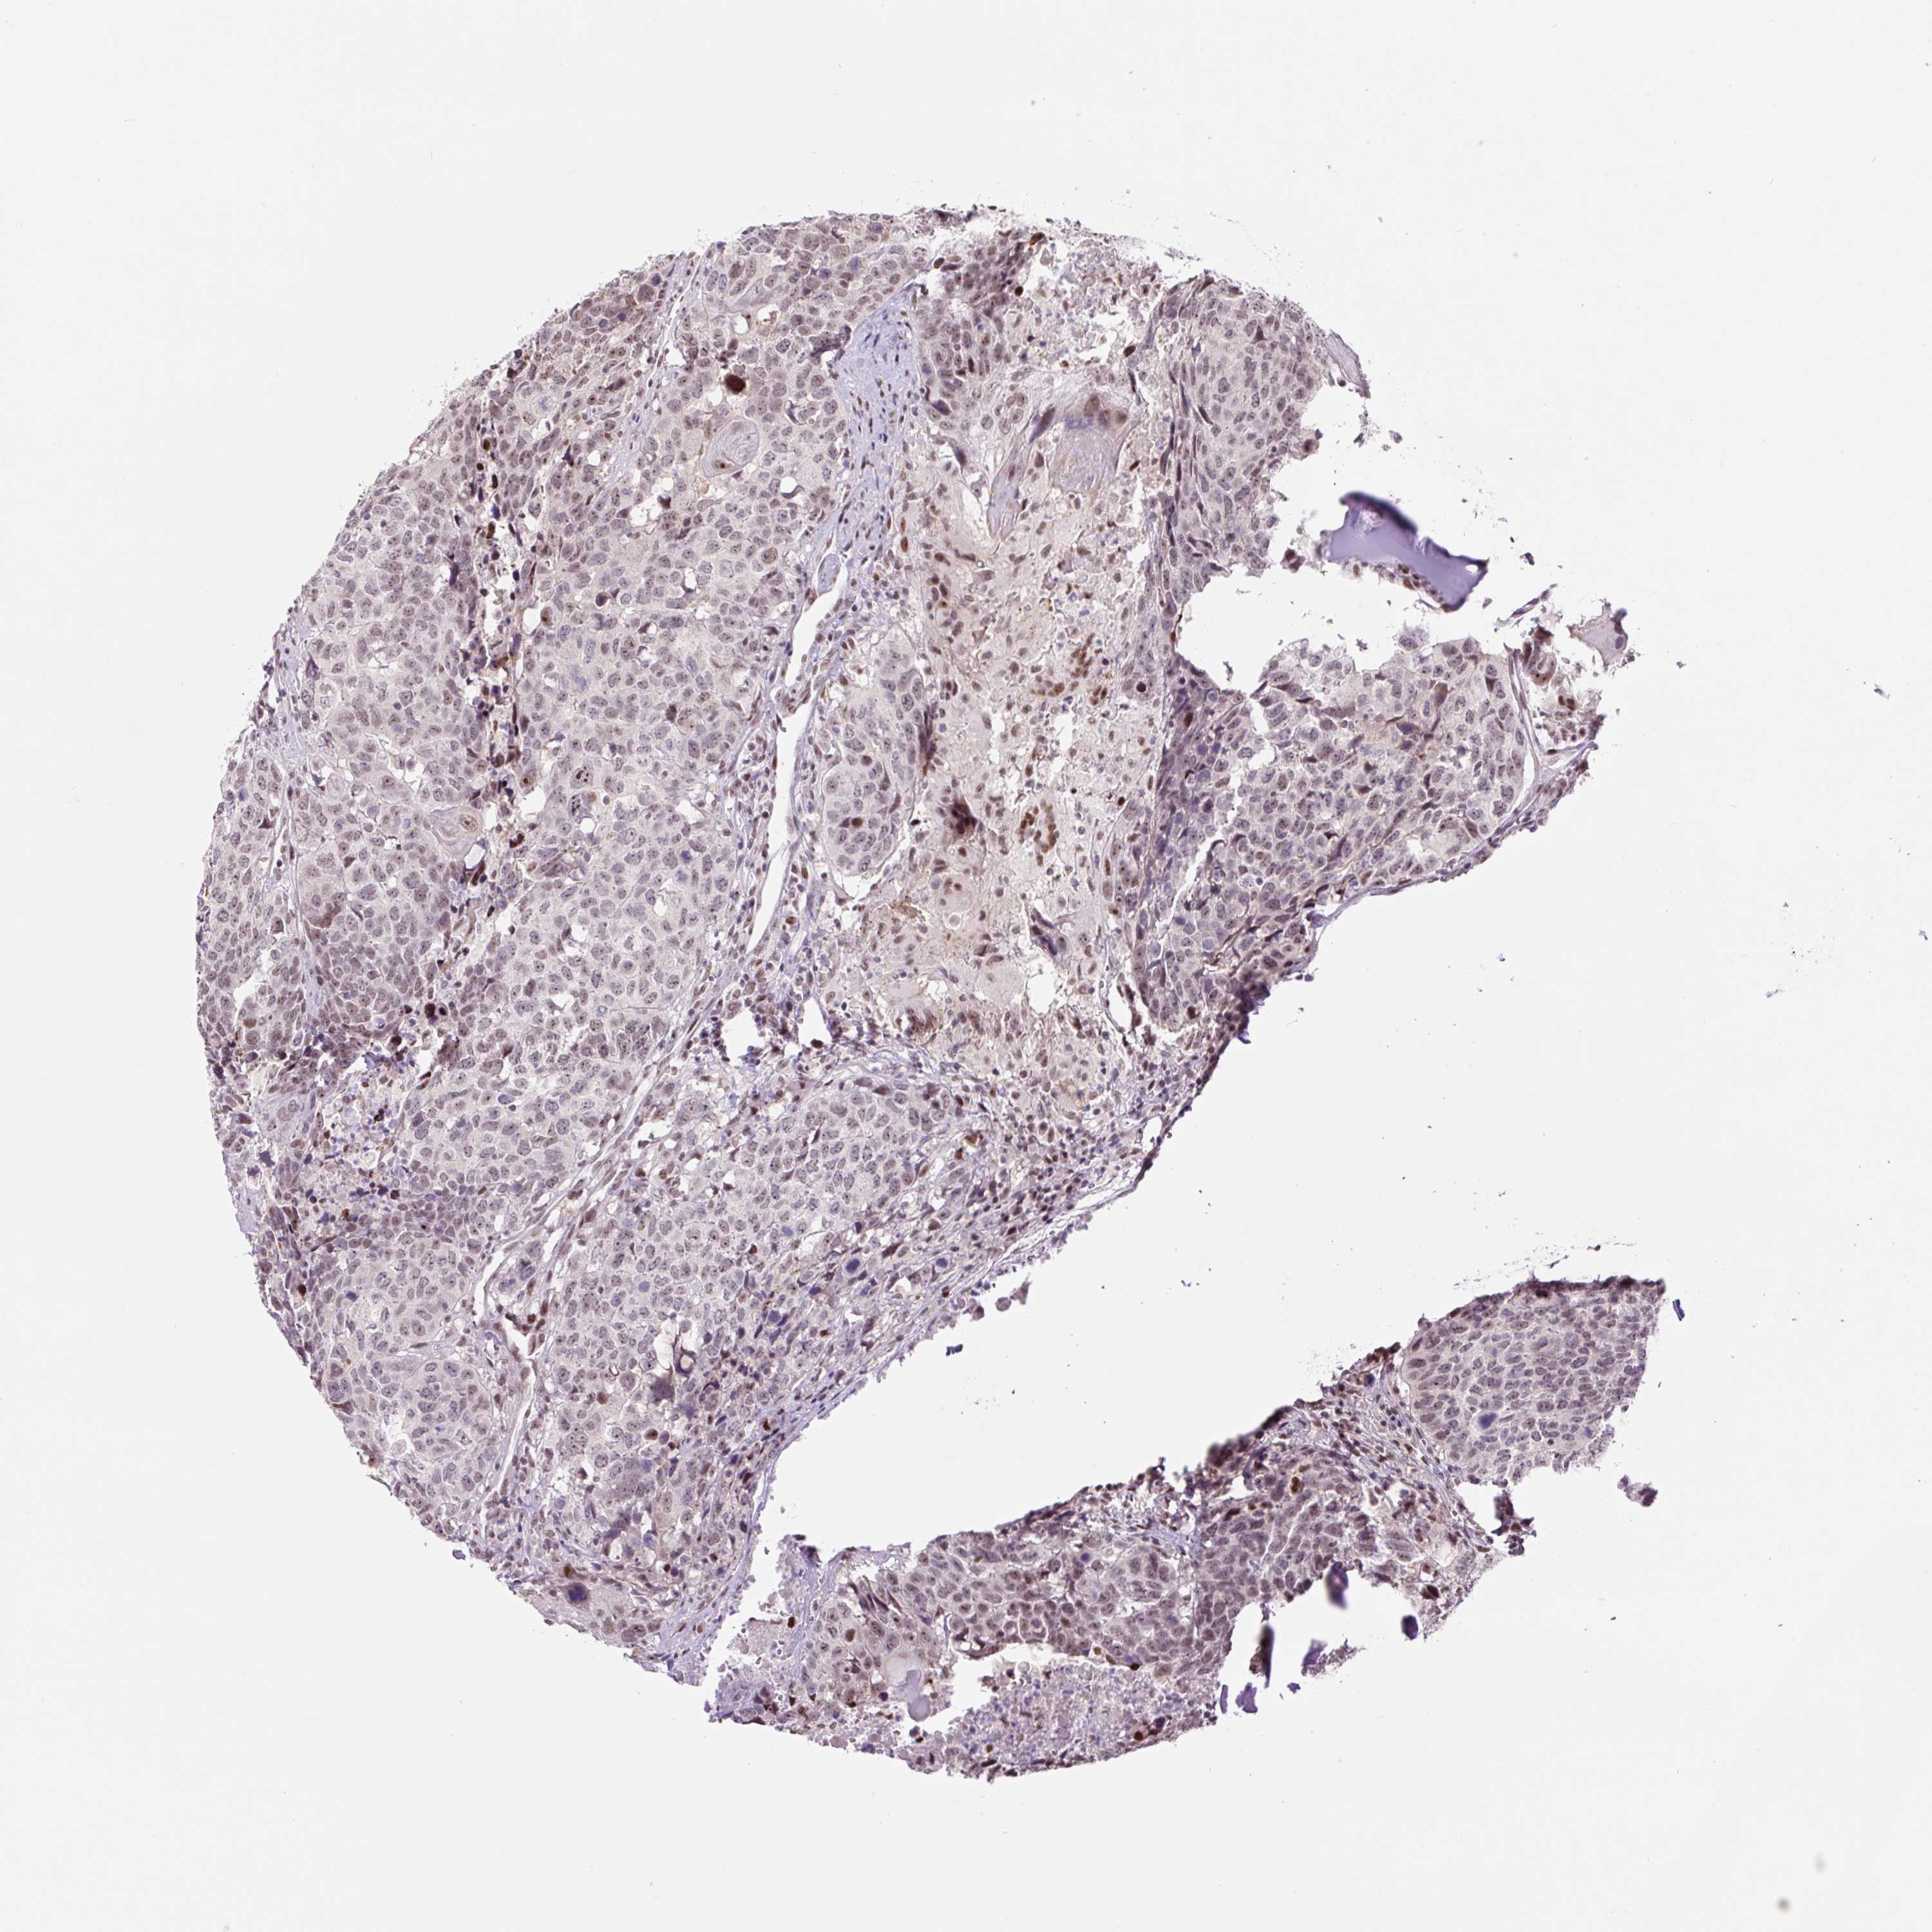

HEAD AND NECK CANCER - Protein expressioni

A mouse-over function shows sample information and annotation data. Click on an image to view it in a full screen mode. Samples can be filtered based on level of antibody staining by selecting one or several of the following categories: high, medium, low and not detected. The assay and annotation is described here.

Antibody stainingi

Antibody staining in the annotated cell types in the current human tissue is reported as not detected, low, medium, or high, based on conventional immunohistochemistry profiling in selected tissues. This score is based on the combination of the staining intensity and fraction of stained cells.

Each image is clickable and will lead to virtual microscopy that enables deeper exploration of all samples and also displays staining intensity scores, fraction scores and subcellular localization as well as patient and tissue information for each sample.

Antibody HPA054334

Staining

High

Medium

Low

Not detected

Intensity

Strong

Moderate

Weak

Negative

Quantity

>75%

75%-25%

<25%

None

Location

Nuclear

Cytoplasmic/membranous

Cytoplasmic/membranous,nuclear

Squamous cell carcinoma, NOS